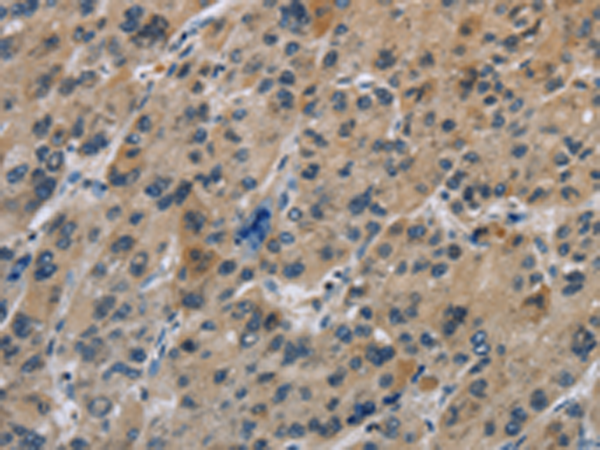

分类: 科研抗体货号: P11826别名: GGF; HGL; HRG; NDF; ARIA; GGF2; HRG1; HRGA; SMDF; MST131应用: WB,IHC反应种属: Human, Mouse